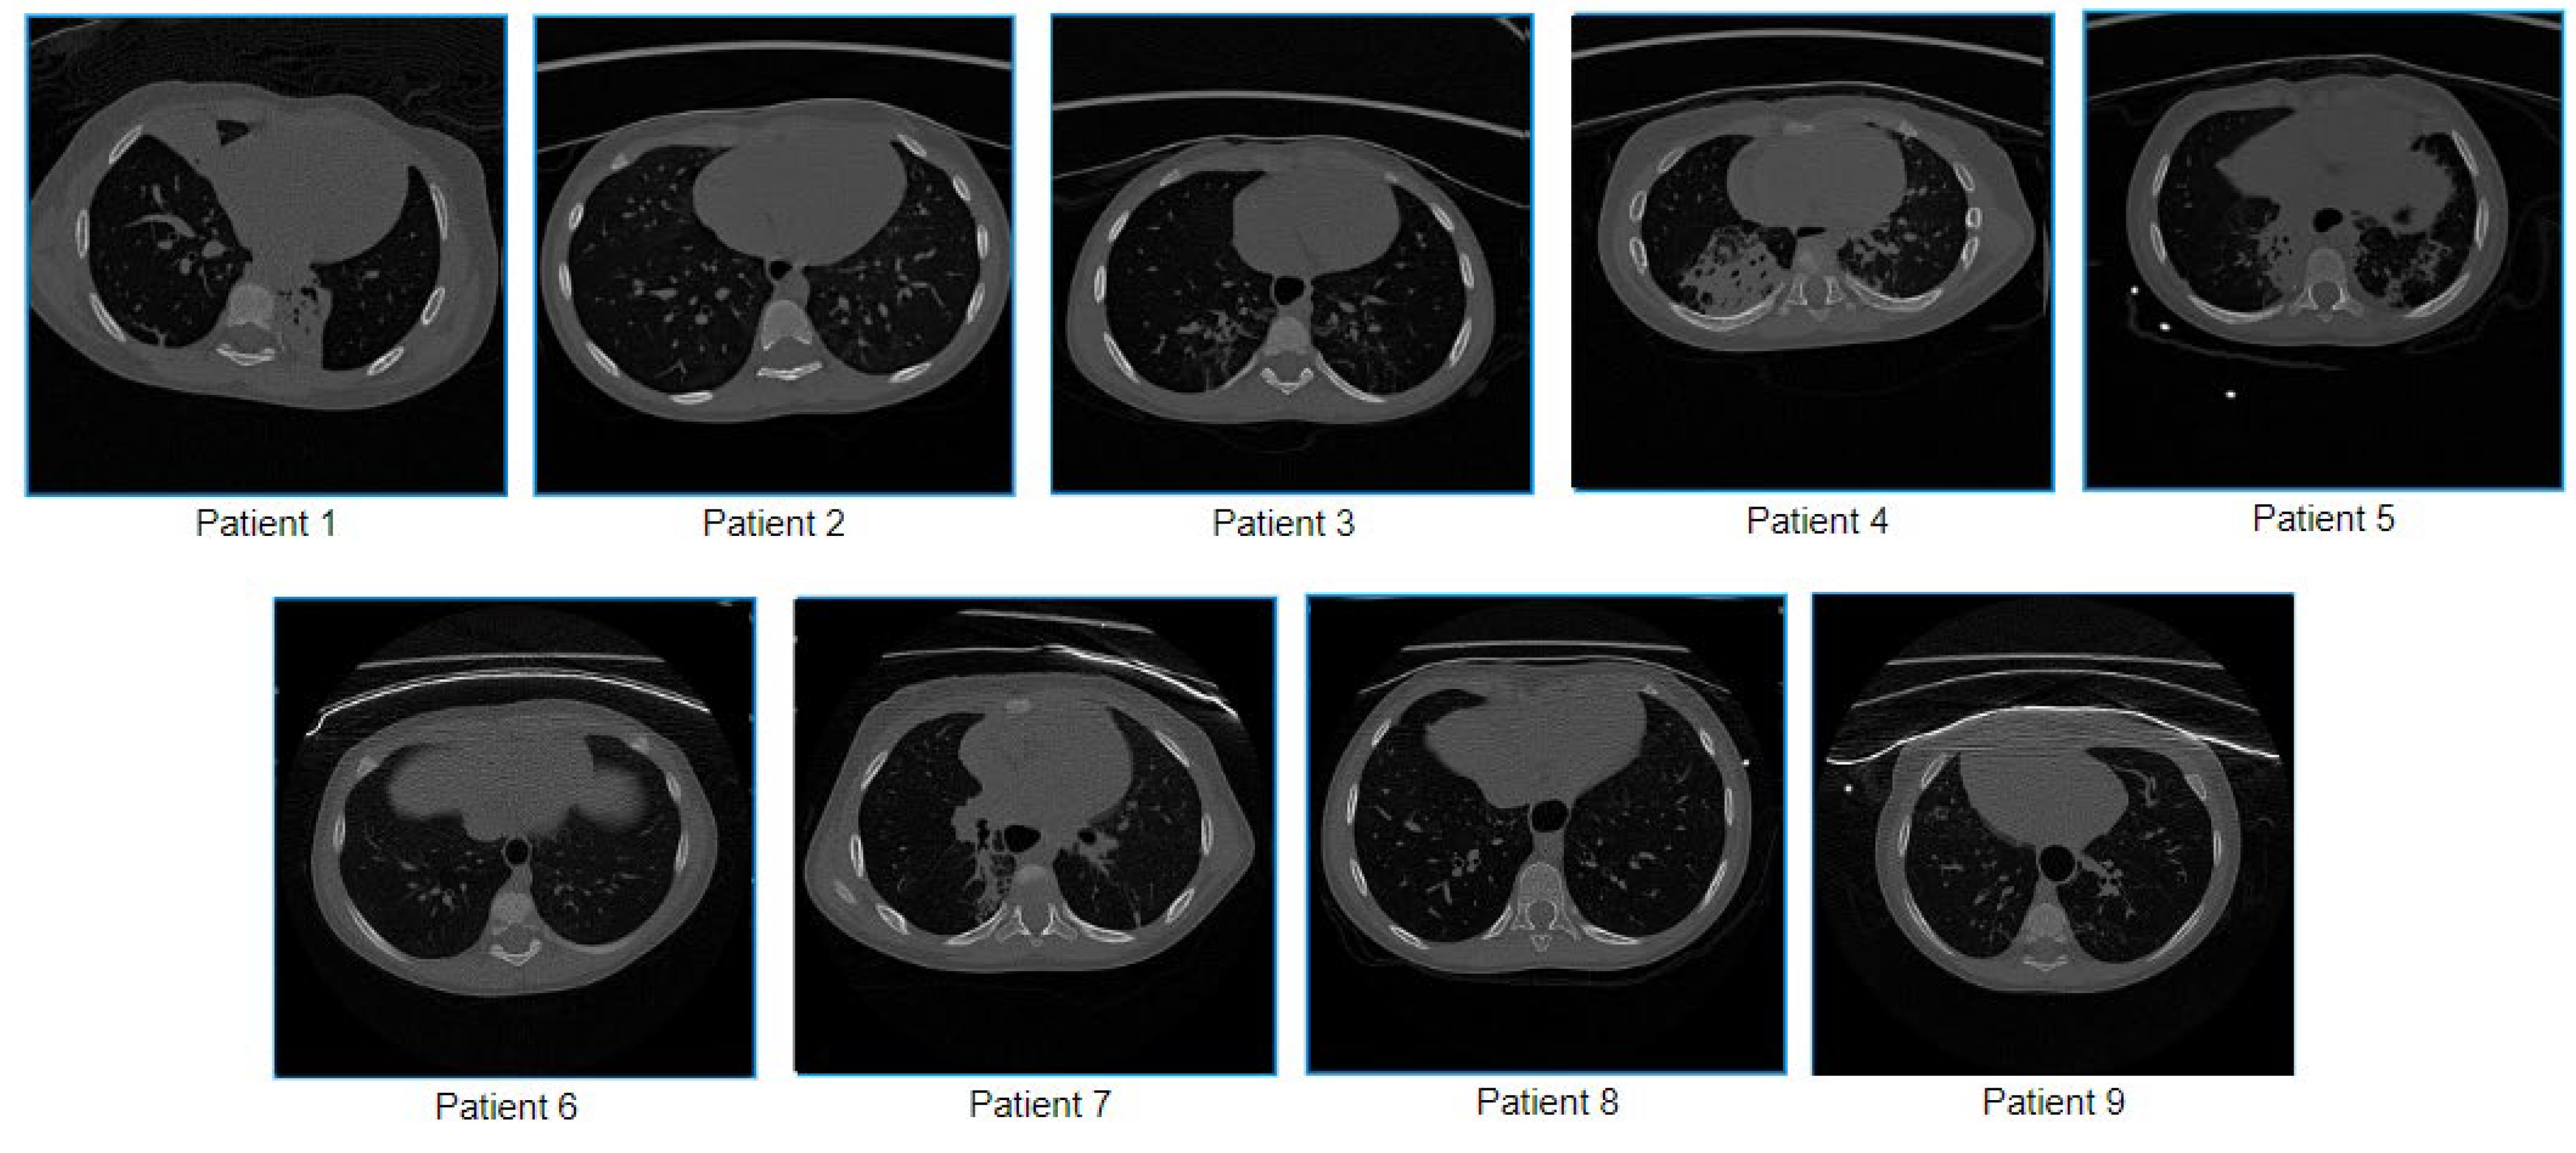

Sample images of the nine children are shown in Figure 1.

Figure 1.

Sample images of nine children utilized in this study.

To suit our computer vision-based approach, the scans are converted to 512 × 512 greyscale images. Patient data such as age, name, and date of birth have been removed from the images.